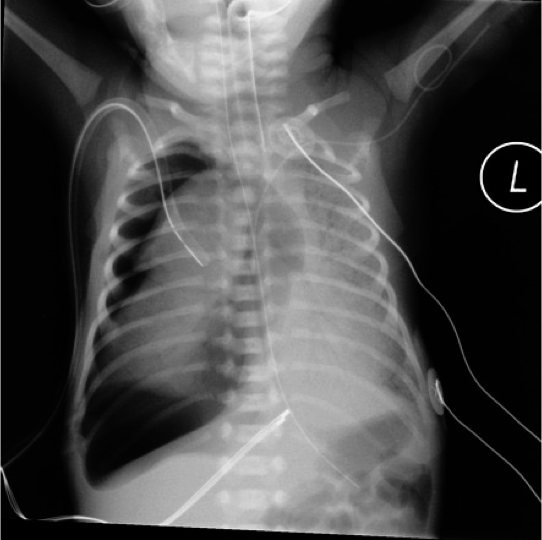

Tension right pneumothorax In Case of Large Pneumothorax

The mediastinum and heart may be pushed to the other side, absent of breath sounds on the ipsilateral side, shifting of cardiac impulse to the contralateral side.